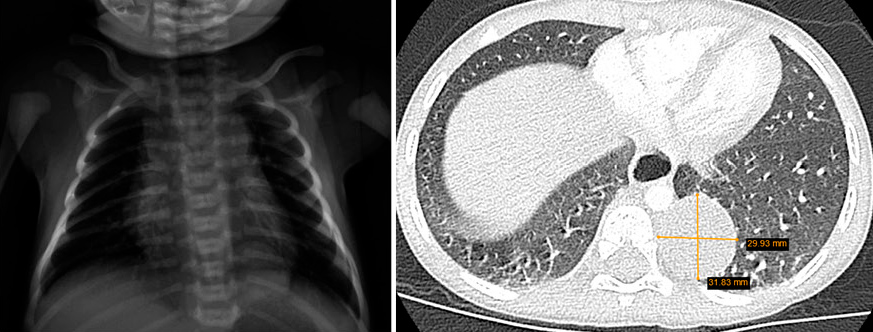

Gestante de 44 años a la que, en el control ecográfico del segundo trimestre, detectan una masa quística pulmonar de 21 x 19 x 17 mm, sin otras malformaciones asociadas. Cribado de cromosomopatías negativo y resto del embarazo sin incidencias, salvo hipotiroidismo subclínico. En controles subsiguientes persiste la masa con leve disminución de su tamaño sin asociar otros hallazgos patológicos. Nace un varón a término con llanto espontáneo, adecuado tono y coloración, con exploración física a las 8 horas de vida sin alteraciones. Ante hallazgos en ecografía prenatal, se solicita una radiografía de tórax que evidencia un aumento de densidad de morfología nodular, de unos 2 cm de diámetro, localizado en campos medios-inferiores derechos, que presenta imágenes radiolucentes milimétricas en su interior (Fig. 6). Es dado de alta sin incidencias a las 48 horas de vida. Figura 6. Radiografía del paciente en el primer día de vida. Se valora de forma presencial en consulta de neumología al mes de vida. El paciente no ha presentado infecciones respiratorias ni episodios de cianosis. Realiza tomas de manera correcta. Adecuado desarrollo ponderoestatural. Patrón respiratorio con rachas de polipnea sin tiraje. Para filiar mejor la lesión, se solicita TACAR, que se realiza a los 2 meses de vida, en el que se observa hipoatenuación e hipovascularización en lóbulo medio sin lesiones quísticas definidas. No efecto masa sobre estructuras mediastínicas ni parénquima pulmonar adyacente. Hallazgos compatibles con enfisema lobar (Fig. 7). Figura 7. TACAR del paciente a los 2 meses de vida. Controles trimestrales durante el primer año de vida. El paciente permanece asintomático. Se deriva a cardiología para descartar cardiopatía estructural asociada. A los 9 meses, radiografía de control que muestra disminución del área hiperdensa respecto al estudio previo.